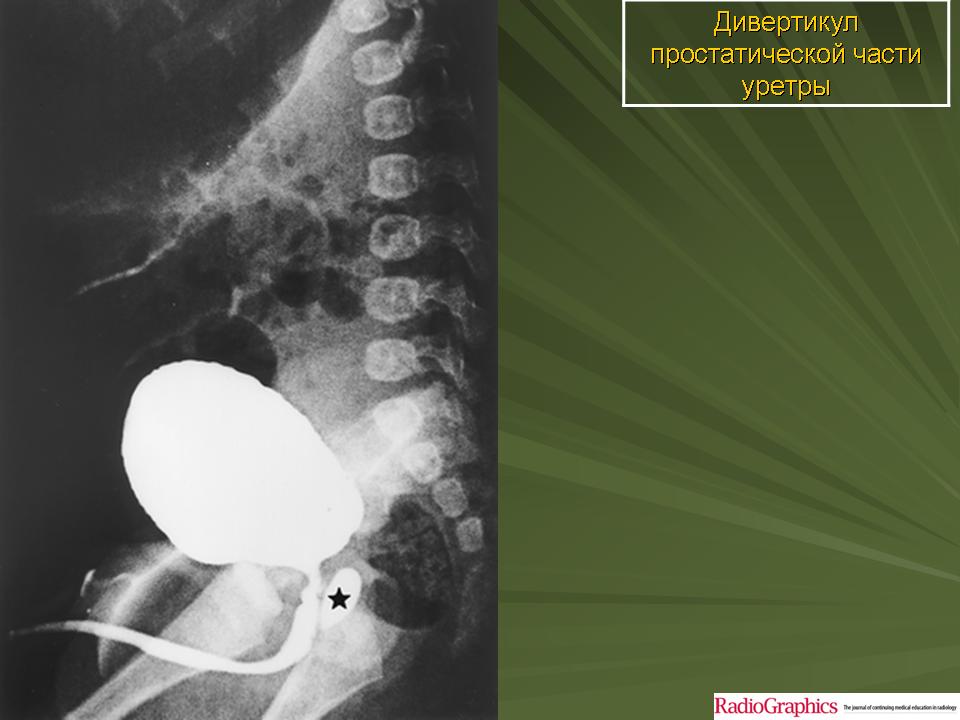

Дивертикулы мочевого пузыря и уретры. Чт, 24/11/2011 - 01:23 #1 Катенёв Валенти... Не на сайте Был на сайте: 7 лет 1 неделя назад Зарегистрирован: 22.03.2008 - 22:15 Публикации: 54876 Дивертикул уретры.Приложения:

Дивертикул уретры.